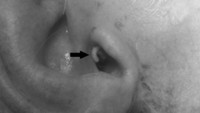

Pemeriksaan klinis menunjukkan lesi erosif atau kerusakan di belakang telinga kanan dengan bekas luka operasi sebelumnya. Setelah mengamati lebih dekat, dokter mengamati beberapa benda asing putih yang mudah bergerak di telinganya dan diambil untuk diperiksa lebih lanjut. Pemeriksaan otoskopi menunjukkan pembengkakan liang telinga luar dan keberadaan larva lalat (miasis) atau belatung. Kasus ini diterbitkan di jurnal Cureus dengan judul 'Aural Myiasis: A Case Report on a Rare Entity' pada 2020. (Foto: Journal Cureus)

Pemeriksaan klinis menunjukkan lesi erosif atau kerusakan di belakang telinga kanan dengan bekas luka operasi sebelumnya. Setelah mengamati lebih dekat, dokter mengamati beberapa benda asing putih yang mudah bergerak di telinganya dan diambil untuk diperiksa lebih lanjut. Pemeriksaan otoskopi menunjukkan pembengkakan liang telinga luar dan keberadaan larva lalat (miasis) atau belatung. Kasus ini diterbitkan di jurnal Cureus dengan judul Aural Myiasis: A Case Report on a Rare Entity pada 2020. (Foto: Journal Cureus)